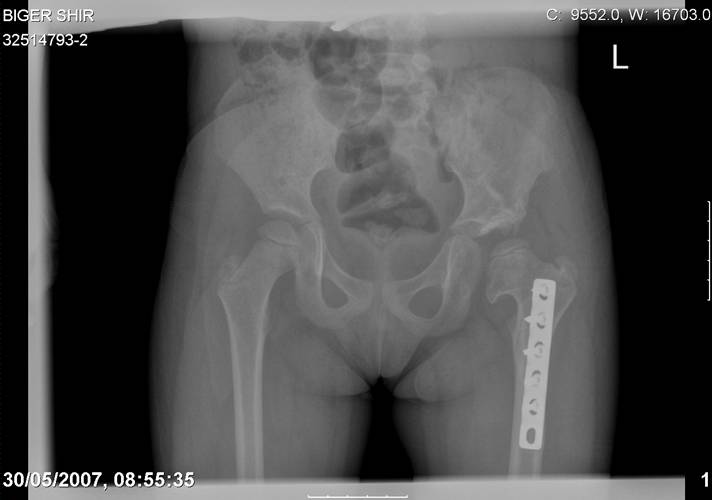

Navernoe Dega

Chto by ne byt goloslovnym posilau vam svoi sluchai gde sdelal vse chto napisal vyshe